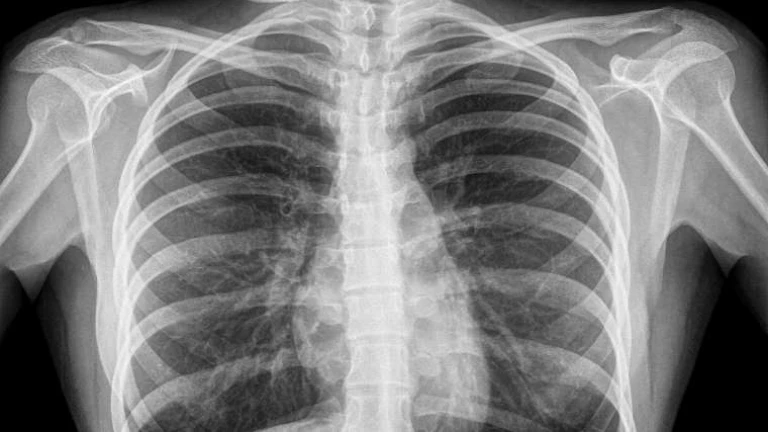

Roberto Pablo explica los riesgos a los que nos sometemos cuando nos hacemos una radiografía o mamografía. Fran Valiño cuenta hasta dónde llegamos para robar cosas de los hoteles. Los chicos de la asociación "Música en Vena" nos presentan su proyecto. David Otero trae las efemérides del día.